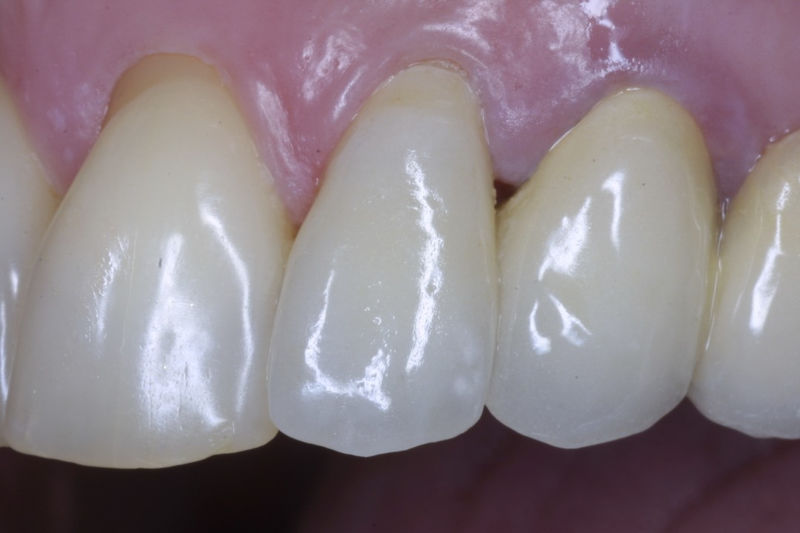

Son restauraciones que cubren toda la cara frontal del diente, generalmente empleadas en el sector anterior y cuya finalidad es primariamente estética.

Restauraciones fabricadas en el laboratorio con materiales estéticos, los cuales cubren de manera total dientes anteriores y posteriores. Se utilizan primariamente para restaurar dientes con caries, fracturas y/o defectos amplios, así como soportes de puentes. Para poder enviar el caso al laboratorio se toman impresiones utilizando materiales de impresión o técnicas modernas digitales.

Ortodoncia y coronas.